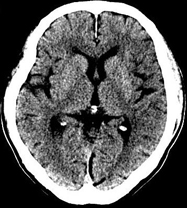

目前臨床對于16層CT的認可主要集中在三維成像領域上的突破.在16層CT的產品平臺上,常規(guī)掃描就能實現(xiàn)滿足三維成像的要求,因此16層也被稱為三維CT,三維成像給臨床診斷帶來了更精確更豐富的診斷信息,我們以臨床為例:

如上圖所示,相鄰的三張軸位圖像未見明顯異常,根據(jù)傳統(tǒng)軸位圖像很難得到準確的臨床診斷。

同一病人利用容積數(shù)據(jù)進行三維處理后,高品質MPR和三維圖像上則清晰顯示了縱向排列的腹腔干與腸系膜上動脈相鄰近,血管發(fā)生變 異,近端血管閉塞,為臨床提供了精確的診斷信息。